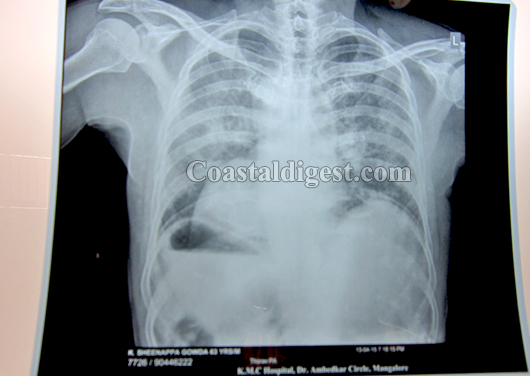

Sheenappa Gowda, 63, Agriculturist from Belthangady knocked the doors of KMC Hospital with complaints of chest pain. On evaluation by eminent cardiologist from KMC Hospital, Dr M N Bhat, it was found that he had his heart on the right than the usual left side and also suffered from heart attack.

Following this revelation he was immediately taken for a coronary angioplasty which showed a single block in the coronary artery. What followed next was a procedure that involved the best medical minds, putting on table the latest technology, innovation of the finest kind and a clinical finesse that together chartered this medical marvel and made the surgery a success. This complicated procedure was done on April 14, 2015 at KMC Hospital. The coronary angioplasty and stenting was very challenging as the hardware are designed for a left sided heart and not for the right like Mr. Sheenappa had.